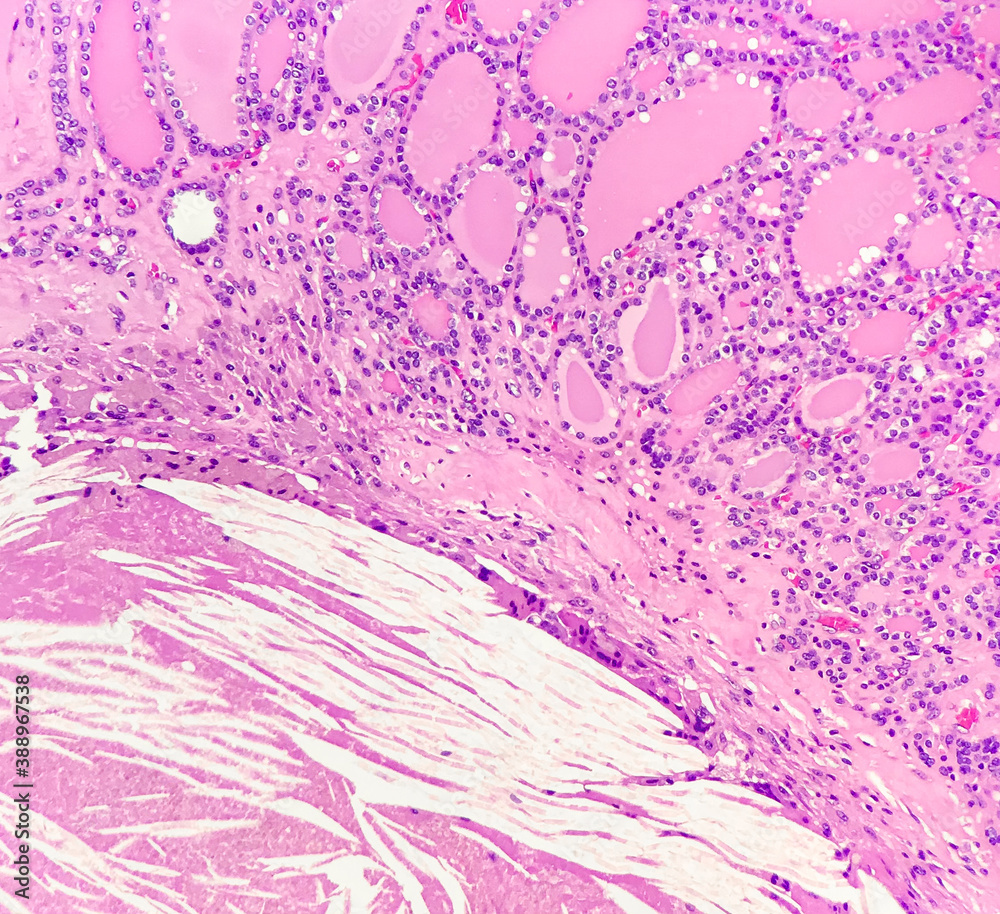

Photomicrograph of the ascending colon. A Cholesterol crystal clefts

Photomicrograph of the ascending colon. A Cholesterol crystal clefts Cholesterol Clefts Once in the tissue, cholesterol tends to clump together to form little droplets that pathologists call cholesterol clefts. Learn how to diagnose and. When cells become damaged or break down, the cholesterol in the cell wall is released into the tissue surrounding the cell. The histology of cholesterol emboli should show diagnostic cholesterol crystals or clefts within the blood vessel. Cholesterol Clefts.